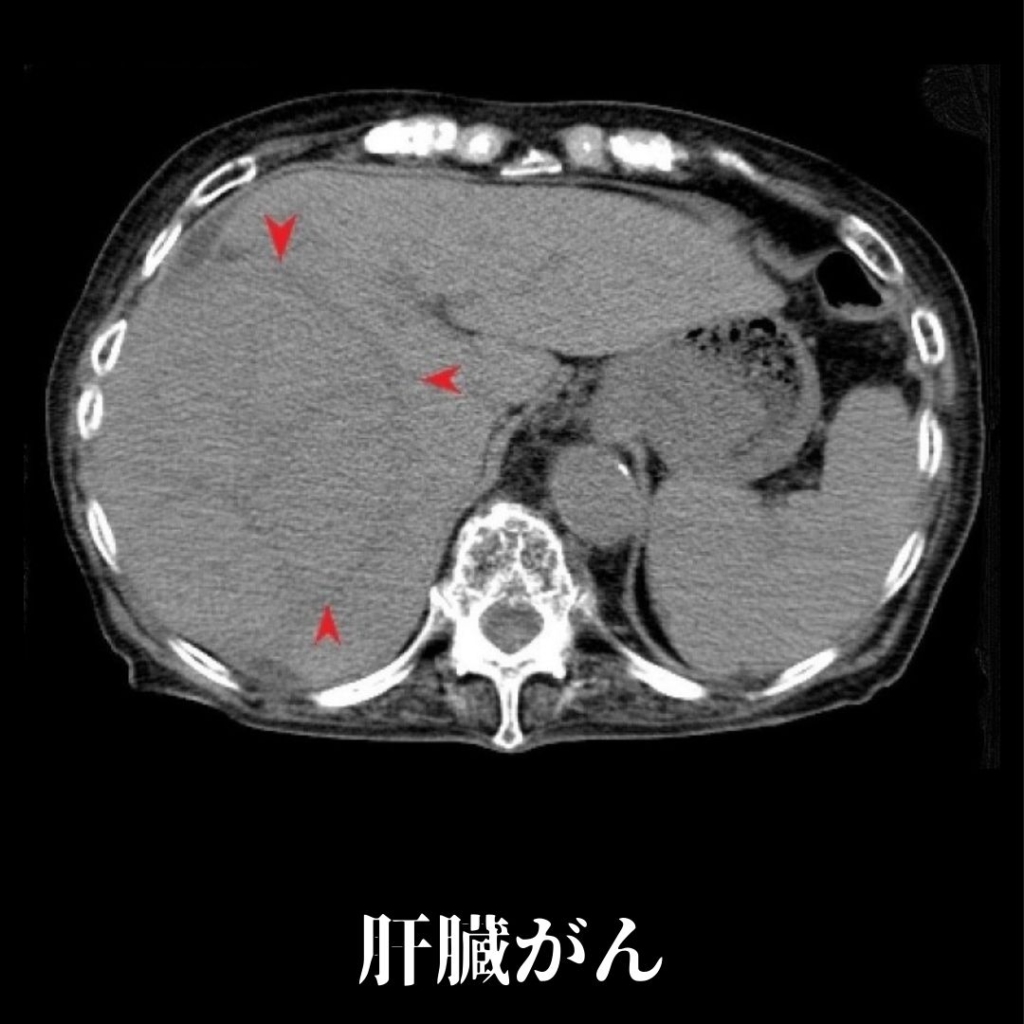

16列マルチスライスCTを完備

当院では、16列マルチスライスCTを完備しております。CTとは、Computed Tomographyの略で、X線を使って身体の断面を撮影することが可能な検査となります。短時間での検査ができ、多くの情報を得ることができます。

脳疾患(脳梗塞、脳出血ほか)、胸部疾患(肺気腫、気胸、肺腫瘍、肺がんほか)、腹部疾患(胃がん、大腸がん、すい臓がん、肝臓がんほか)、骨折等の整形外患ほか、多岐にわたる検査が可能です。